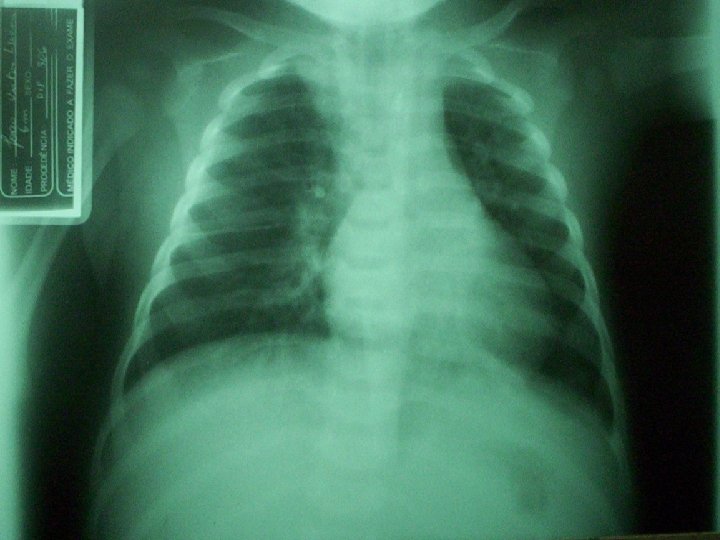

MANIFESTAÇÕES CLÍNICAS n n Achados da radiografia: infiltrados intersticiais ou doença alveolar difusa que progride rapidamente. Às vezes surgem lesões nodulares, infiltrados raiados ou lobares, derrames pleurais. Diagnóstico: Demonstração do P. carinii por coloração apropriada com prata de lavado broncoalveolar; raramente a biópsia é necessária.

MANIFESTAÇÕES CLÍNICAS n n n Diagnóstico: RX de tórax com infiltrados difusos, hiperinsuflação. Contagem de leucócitos normal ou levemente elevada (<20000), com linfócitos predominantes. Reagentes de fase aguda normais ou levemente aumentados. Diagnóstico definitivo: Isolamento do vírus em amostra do trato respiratório e sorologias.

MANIFESTAÇÕES CLÍNICAS n n n Contagem de leucócitos elevada, com predomínio de polimorfonucleares. Gasometrias arteriais mostram hipoxemia, sem hipercapnia. Achados Radiográficos: consolidações, infiltrado e derrame em alguns casos. Tratamento: Penicilina G, se S. pneumoniae resistente, cefalosporinas de terceira geração. Caso haja resistência com estes últimas, vancomicina (CULTURA)

MANIFESTAÇÕES CLÍNICAS n n n Manifestações e laboratório similares ao das outras PNM bacterianas. RX: grandes derrames pleurais e pneumatoceles. Elevação da ASLO. Swab de orofaringe, secreções nasofaríngeas ou escarro. Tratamento: Penicilina G

MANIFESTAÇÕES CLÍNICAS n n PNEUMONIA ESTAFILOCÓCICA Causam broncopneumonia confluente, muitas vezes unilateral, ou mais proeminente em um dos lados (RX compatível). Numerosos abcessos, podendo ocorrer piopneumotórax.

MANIFESTAÇÕES CLÍNICAS n n n PNEUMONIA POR HAEMOPHILUS INFLUENZAE Vacina Início insidioso e longa evolução. Tosse sem expectoração, tiragem e batimento de asas do nariz, febre, taquipnéia e macicez localizada à percussão, estertores e sopro tubário. RX – líquido pleural